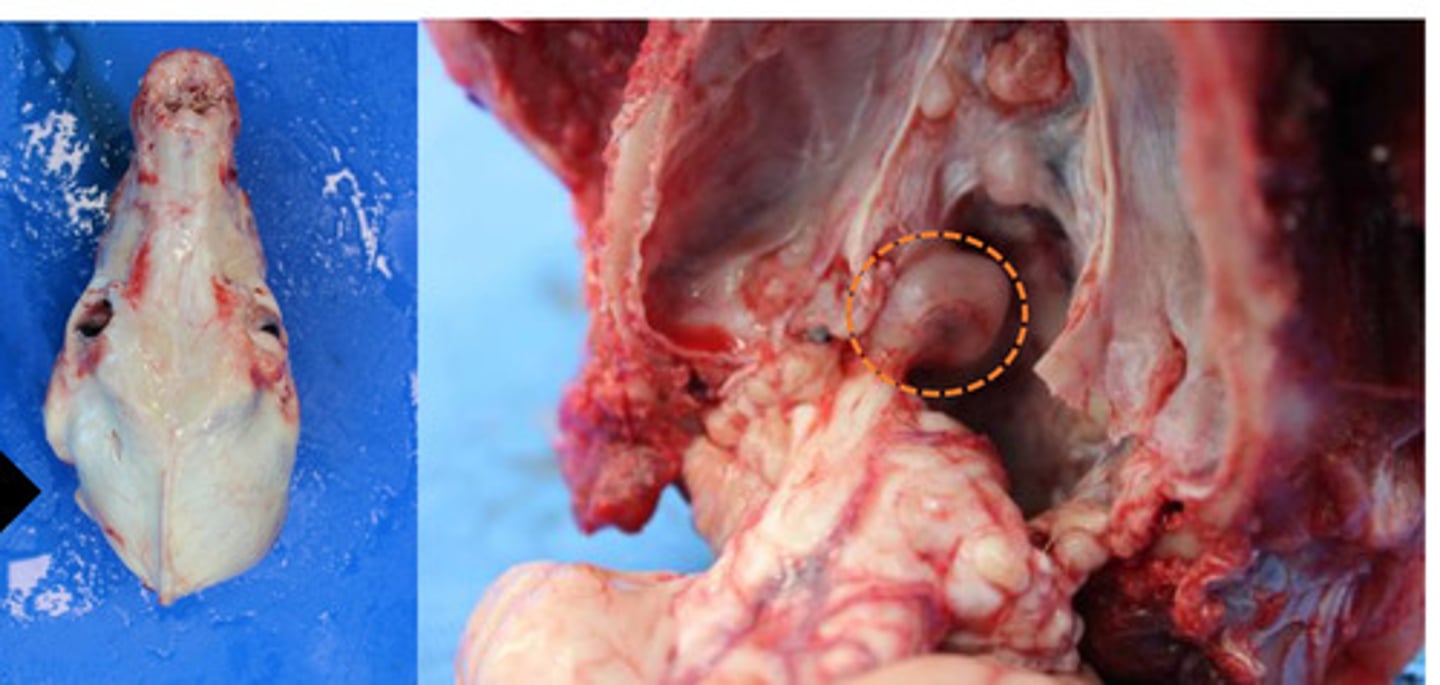

Identify the pathology:

Ostosarc